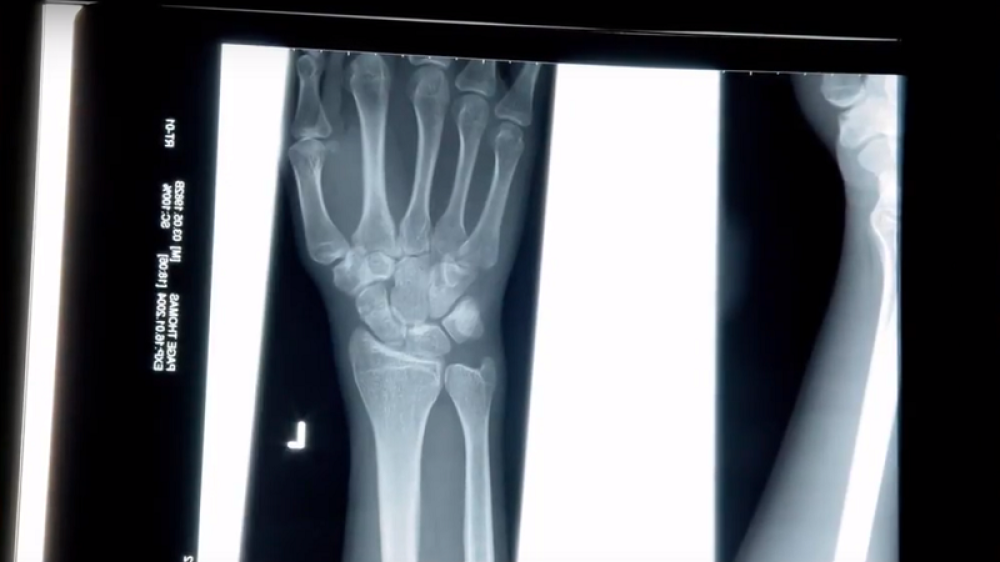

Veštačka inteligencija detektuje i najsitnije prelome kostiju